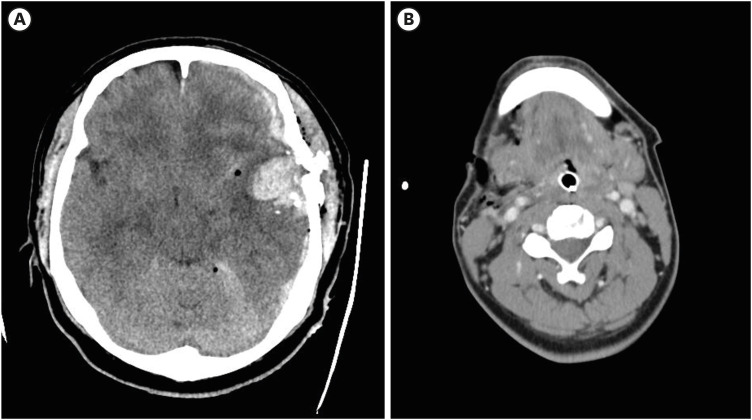

We present a unique case of a gunshot wound to the head and neck in a 51-year-old male in Korea, where such injuries are extremely rare. The case involved complex emergency procedures including neurosurgery and lingual artery ligation, complicated by worsening cerebral conditions. This report contributes to the limited Korean literature on such injuries, providing insights into their management and the importance of immediate multidisciplinary medical interventions for gunshot trauma.